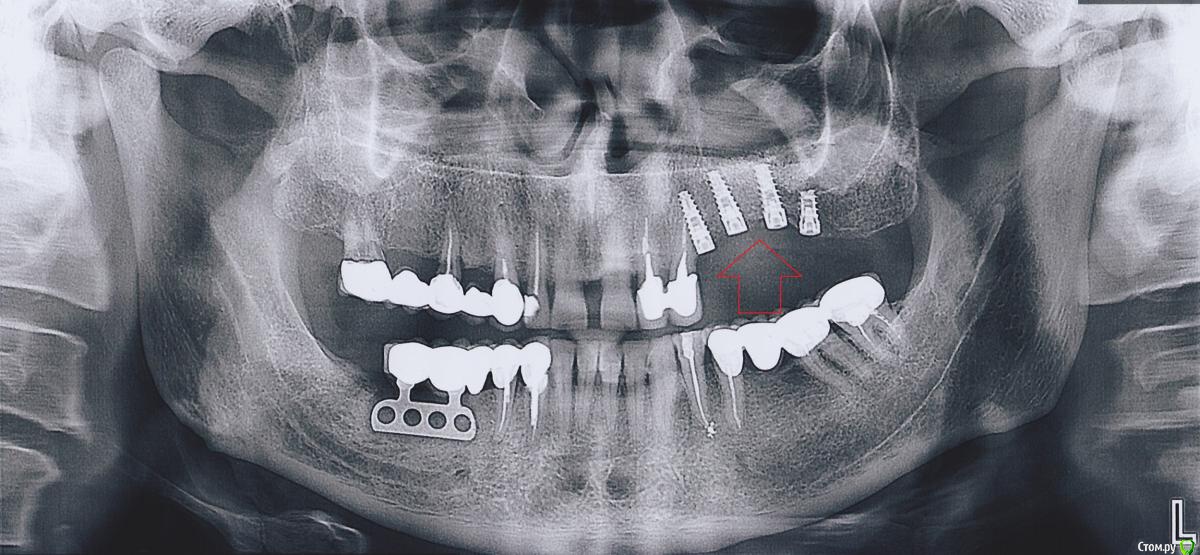

pistons777 Опубликовано 17 ноября, 2018 Поделиться Опубликовано 17 ноября, 2018 Здравствуйте, 3 года назад были установлены в верхнюю челюсть 4 импланта с наращиванием кости.Через 6-7 месяцев был установлен мост.2 месяца назад (мост начал слегка шататься (дышать, почвакивать…)Обратился к доктору, сделали снимок который показал, что импланты в порядке и скорее всего отклеился мост, попытались снять мост, но безуспешно.После чего было принято решение ждать, чтоб больше расшатался мост.Спустя месяц, мост стал намного больше шататься, но снять не получилось т.к. при попытке вытащить, его как будто клинит.Теперь стоит вопрос распилить мост и разбираться, что произшло.Если проблема с абатментом или абатментами нужно знать производителя, а он неизвестен т.к. устанавливались одним доктором, а другой доктор сейчас решает эту проблему. Так сложилась ситуация, географически. Спасибо, за вашу помощь! Ссылка на комментарий

Nazim_NV86 Опубликовано 18 ноября, 2018 Поделиться Опубликовано 18 ноября, 2018 Здравствуйте. Систем имплантации сейчас сотни. Журнал операций должен быть, с датой и наклейками от имплантов. По звонку узнать не пробовали? (Похожи на альфа био spi) 1 Ссылка на комментарий

Bier Опубликовано 19 ноября, 2018 Поделиться Опубликовано 19 ноября, 2018 имплантаты похожи на израильские. Там почти у всех систем стандартно все. Alpha-Bio как вариант. Ссылка на комментарий